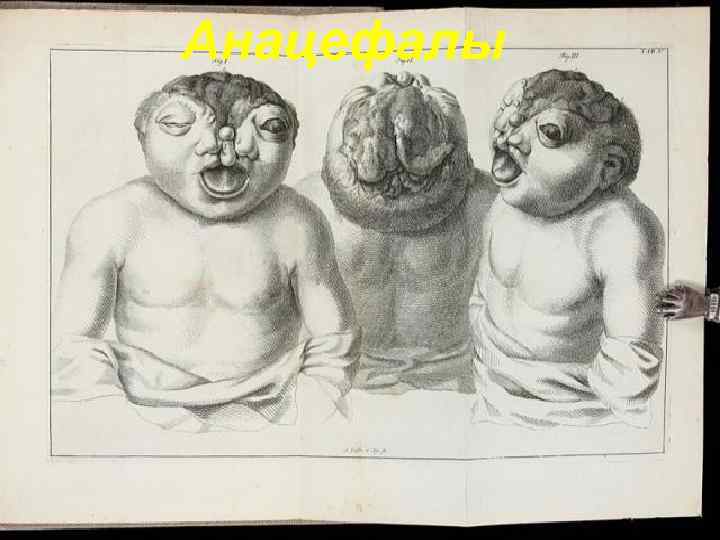

Анацефалы 129

Анацефалы. Многочисленные анатомические дефекты развития черепа. Из книги «Specimen Observationum Academicarum, ad Monstrorum Historiam, Anatomen, Pathologiam, et Artem Obstetriciam, Praecipue Spectantum» , 1765 130